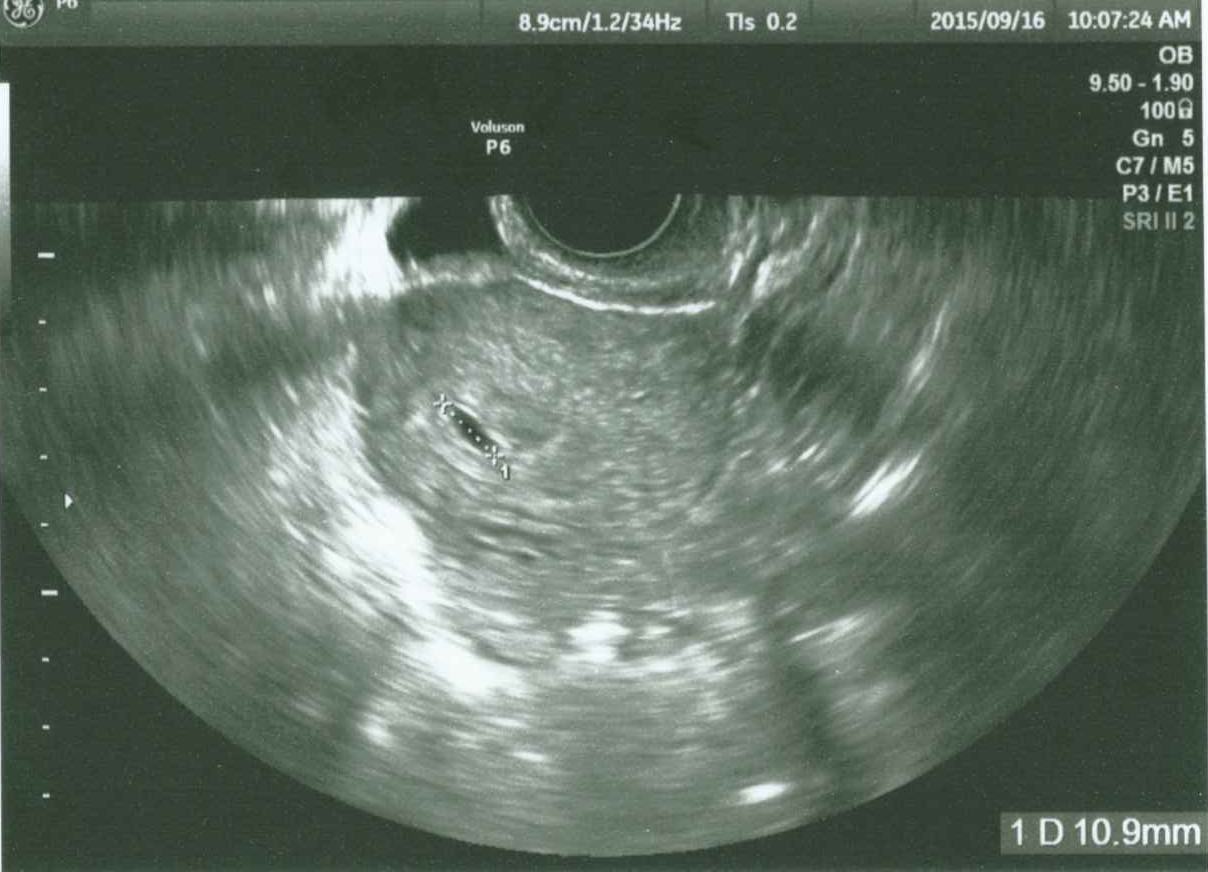

妊娠4週目 4w0d 6d のエコー写真とエピソード 妊娠2ヶ月 Cozre コズレ 子育てマガジン

妊娠4週目のエコー写真 胎芽や胎嚢 初期症状や流産のこと 妊娠初期 All About

マタニティライフ 妊娠から出産までの記録 妊娠4週目エコー画像

妊娠4週0日 4w0d の超音波 エコー 写真

妊娠4週4日 エコー写真 私と赤ちゃんと時々し ちゃん

2007 3 16 4週5日 スヌーピーの日記

妊娠4週6日目 初めての検診 たまちゃんといっしょ

4週5日目 病院で妊娠を確認 妊娠と出産と それから

妊娠4週 3 6日 のエコー写真 体験談

妊娠4週5日目 超音波写真 Paparinko S Diary

妊娠4週3日 4w3d の超音波 エコー 写真

妊娠4週4日 4w4d の超音波 エコー 写真